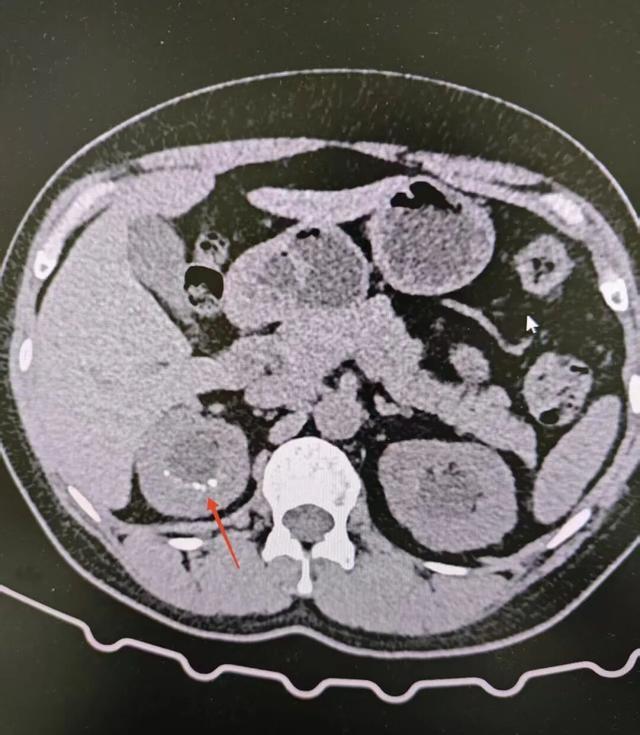

45岁的李女士(化名),因结石反复发作而苦恼,多次手术消除石头,但是结石像割不完的韭菜,术中显示:密密麻麻的结石斑点,一半扎在组织里,一半探出肾盏。李女士被诊断为髓质海绵肾,它让李女士的肾脏成了一块天生就容易滋生结石的“温床”。

为了帮助她解决梗阻性结石,科室采用输尿管软镜钬激光碎石术,经自然腔道进入肾脏,精准击碎并取出“冒尖”的结石,术后第二天她即可下床活动,根据体质,团队为她制定了个性化调理方案,包括中药内服、健康饮食与生活方式指导,并建立健康档案动态跟进,术后复查CT显示,肾脏内未形成新的梗阻性结石,微小“竹笋尖”也保持稳定。

很多人一听“髓质海绵肾”就紧张,其实它不是肿瘤,也不是炎症,而是天生的肾发育异常,肾脏里排尿的微小管道末端天生形成许多小囊泡,让肾脏像海绵一样多孔,尿液滞留其中,矿物质慢慢沉积,便形成了星罗棋布的微小结石,结石反复发作的根源就在这,所以,科学管理不能只盯着石,更要关注长石头的“土壤”。